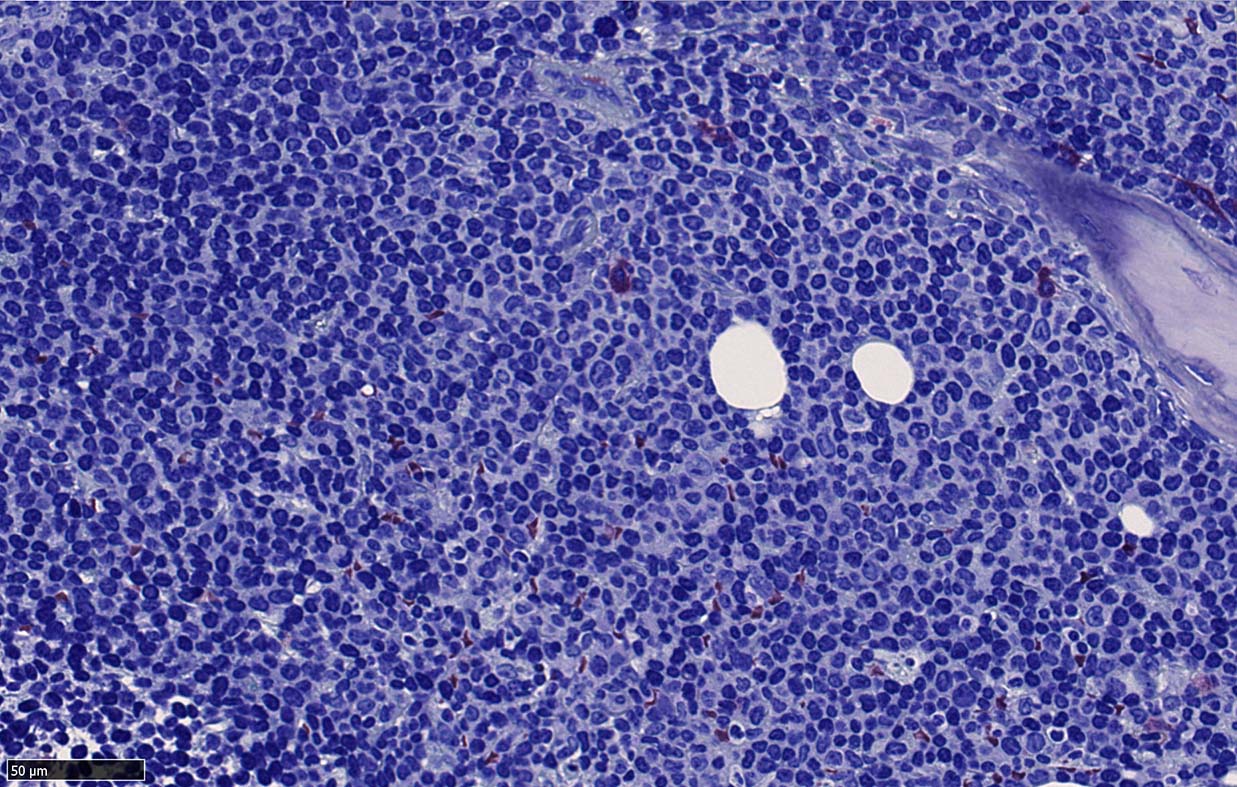

Bone marrow involvement of mantle cell lymphomaの症例

骨髄骨梁間に密なASD-Giemsa陰性の小型~中型円形細胞の浸潤が認められる.

MCLは60-90%の症例で骨髄に浸潤する. *1*2*3*4*5. 骨髄浸潤の最も一般的なパターンは, focal random(限局性, ランダム)で, 80%以上の症例でみられる.

骨梁間(interstitial)には約50%, びまん性浸潤は20~30%の症例でみられる。*1,*6 とくに, 傍骨梁浸潤は45%の症例に認められる. 時には、濾胞性リンパ腫に似た傍骨梁のみの浸潤を認めることもある. まれに、顕著な類同内浸潤を伴う症例も報告されている。*7